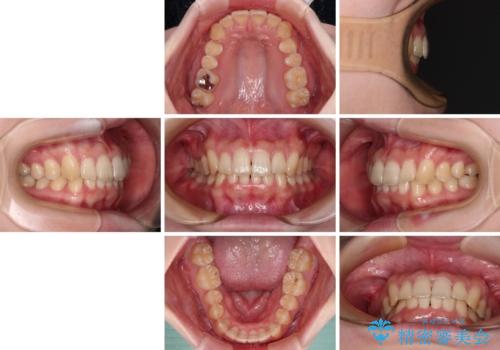

- 全体的な歯列の叢生を気にして来院された患者様です。

奥歯の咬み合わせを見ると、片方は上顎が下顎に対して相対的に前方にあり、他方は交叉した咬合の状態でした。

咬み合わせを改善するためには、上顎臼歯を後方に移動させた咬み合わせにする必要があります。

インビザライン単体で改善することも可能ですが、ディープバイトのためインビザライン単体で達成する可能性が低いと考えられたため、カリエール・ディスタライザーという補助装置を併用して、より確実性を上げることとしました。